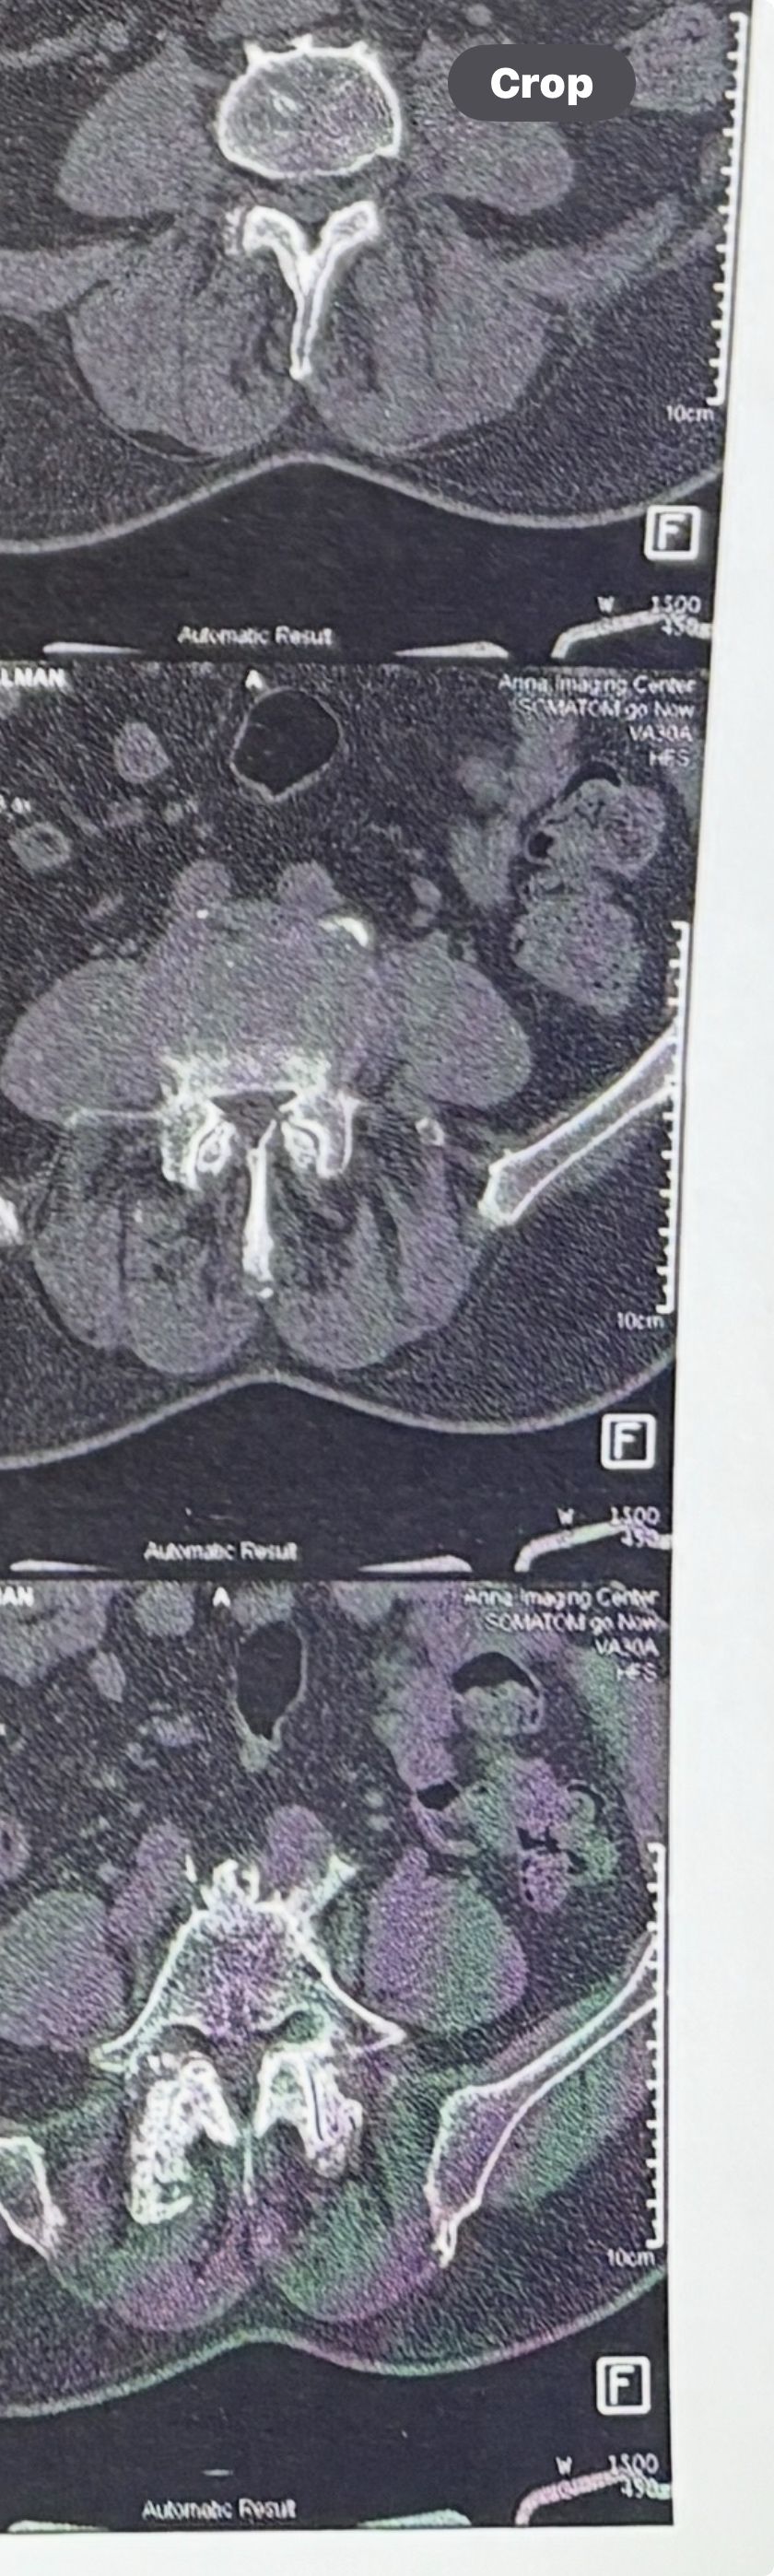

Few weeks ago I posted a case with an old TB spondylitis and listhesis with old fractures and severe canal stenosis (in her lower lumbar). A neurosurgeon who works with us at my clinic saw her in the second session

I attached her CT scan. Her PPD which was positive 2 months ago now it’s less than 3 mm. Since this patient has just low back pain and no radicular pain and can walk easily our neurosurgeon suggested no surgery and we emphasized that she has to complete her medication and be under her infectious diseases specialist

And if other signs and symptoms develops have to see surgeon again

42 years old female presented to my clinic yesterday on May15/2025 with chronic Low back for 2 yrs. She is from afghanestan and arrived to tehran 3 month ago. Visited pain specialist 3 months ago who just did PPD test and gave her Anti TB medication. In examination just had severe focal khyphosis from L3 to L5 without any tenderness. Her mri was done 2 months ago. Report is in Farsi and mentions of paraspinal puss/ fluid collection esp in psoas muscles, with extension of fluid collection to R pelvic region. Had 2 site of severe canal stenosis due to previous fractures of L3,4,5 and movement of fractured bones to the canal with complete distractions of those levels discs with fusion of L3 to L5

I ordered C T scan of lumbar and pelvic MRI / chest x r and reffered her to neurosurgon and infectious disease specialist to get full assessment and possible hospitalized for biopsy and surgery

As you know doctors of chiropractic would never. give treatment to patients with spinal Discitis/ osteomyelitis/ metastasis/ fracture( absolute chiropractic contraindications for treatment)